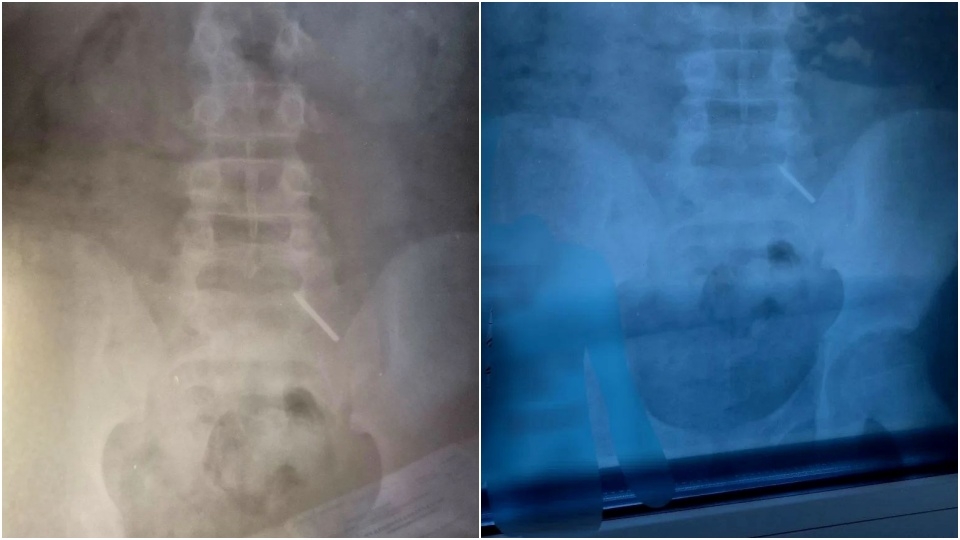

В клинику поступил 11-летний школьник, который, как оказалось, проглотил часть циркуля.

"Эндоскопически достать предмет не представлялось возможным из-за позднего обращения пациента. Главной задачей было не допустить перфорации кишечника и кровотечения - мальчик находился под наблюдением врачей и рентгенологов. В итоге инородное тело вышло естественным путем. Пациент выписан домой", - рассказали в больнице.